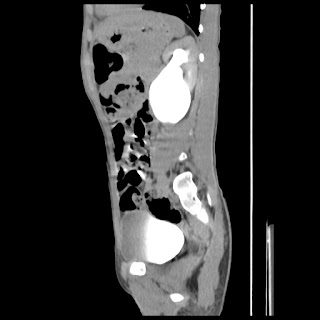

A 07 years old child with left side of abdomen pain

current CT images: